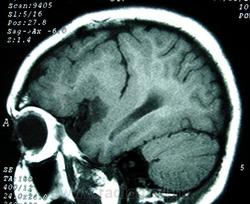

ГМ. Шизэнцефалия. +

Шизэнцефалия характеризуется расщеплением коры головного мозга линеинои формы, которое распространяется от желудочков к субарахноидальному пространству. Предположительно возникновение шизэнцефалии связано с окклюзией средних мозговых артерий, что может объяснить двусторонний характер поражения. В случаях шизэнцефалии нарушение сосудистого питания приводит не столько к разрушению мозговой ткани, сколько к ее неправильному формированию. Сочетание шизэнцефалии с другими аномалиями развития мозга свидетельствует о наличии другого механизма ее возникновения - первичных нарушений в большая часть коры разрушается. Многие из выживших детей страдают тяжелой умственной отсталостью.

Основным диагностическим критерием шизэнцефалии является наличие двусторонних дефектов, исходящих из боковых желудочков в направлении к наружной поверхности коры головного мозга. Обычно дефекты располагаются симметрично, хотя могут быть и односторонними.